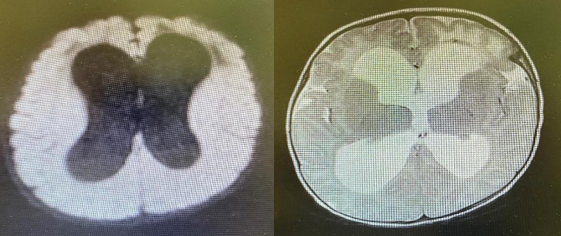

CT /and Magnetic resonance imaging (MRI) brain with contrast was subsequently performed which showed hypo-dense lesion with peripheral enhancement suggestive of intra-parenchymal abscess in left frontal

Figure 1 ?. Head CT: showed a large left frontal hypodense cystic like lesion about 3.5x3.5 cm with density about (13 hu) causing compression of the left lateral ventricle anterior horn with midline shift to the right anteriorly about 3-4 mm with surrounding minimal oedematose changes in both frontal lobes

Figure 2: MRI brain images: There is left frontal intra axial complex cystic  lesion 3.5x3.7x3.9 & thin smooth rim of peripheral enhancement ,internal thin enhancing septation fluid-fluid level and debris causing mass  effect on adjacent  frontal horn with mild midline shift 3mm to the right ,no direct connection seen with the left frontal horn